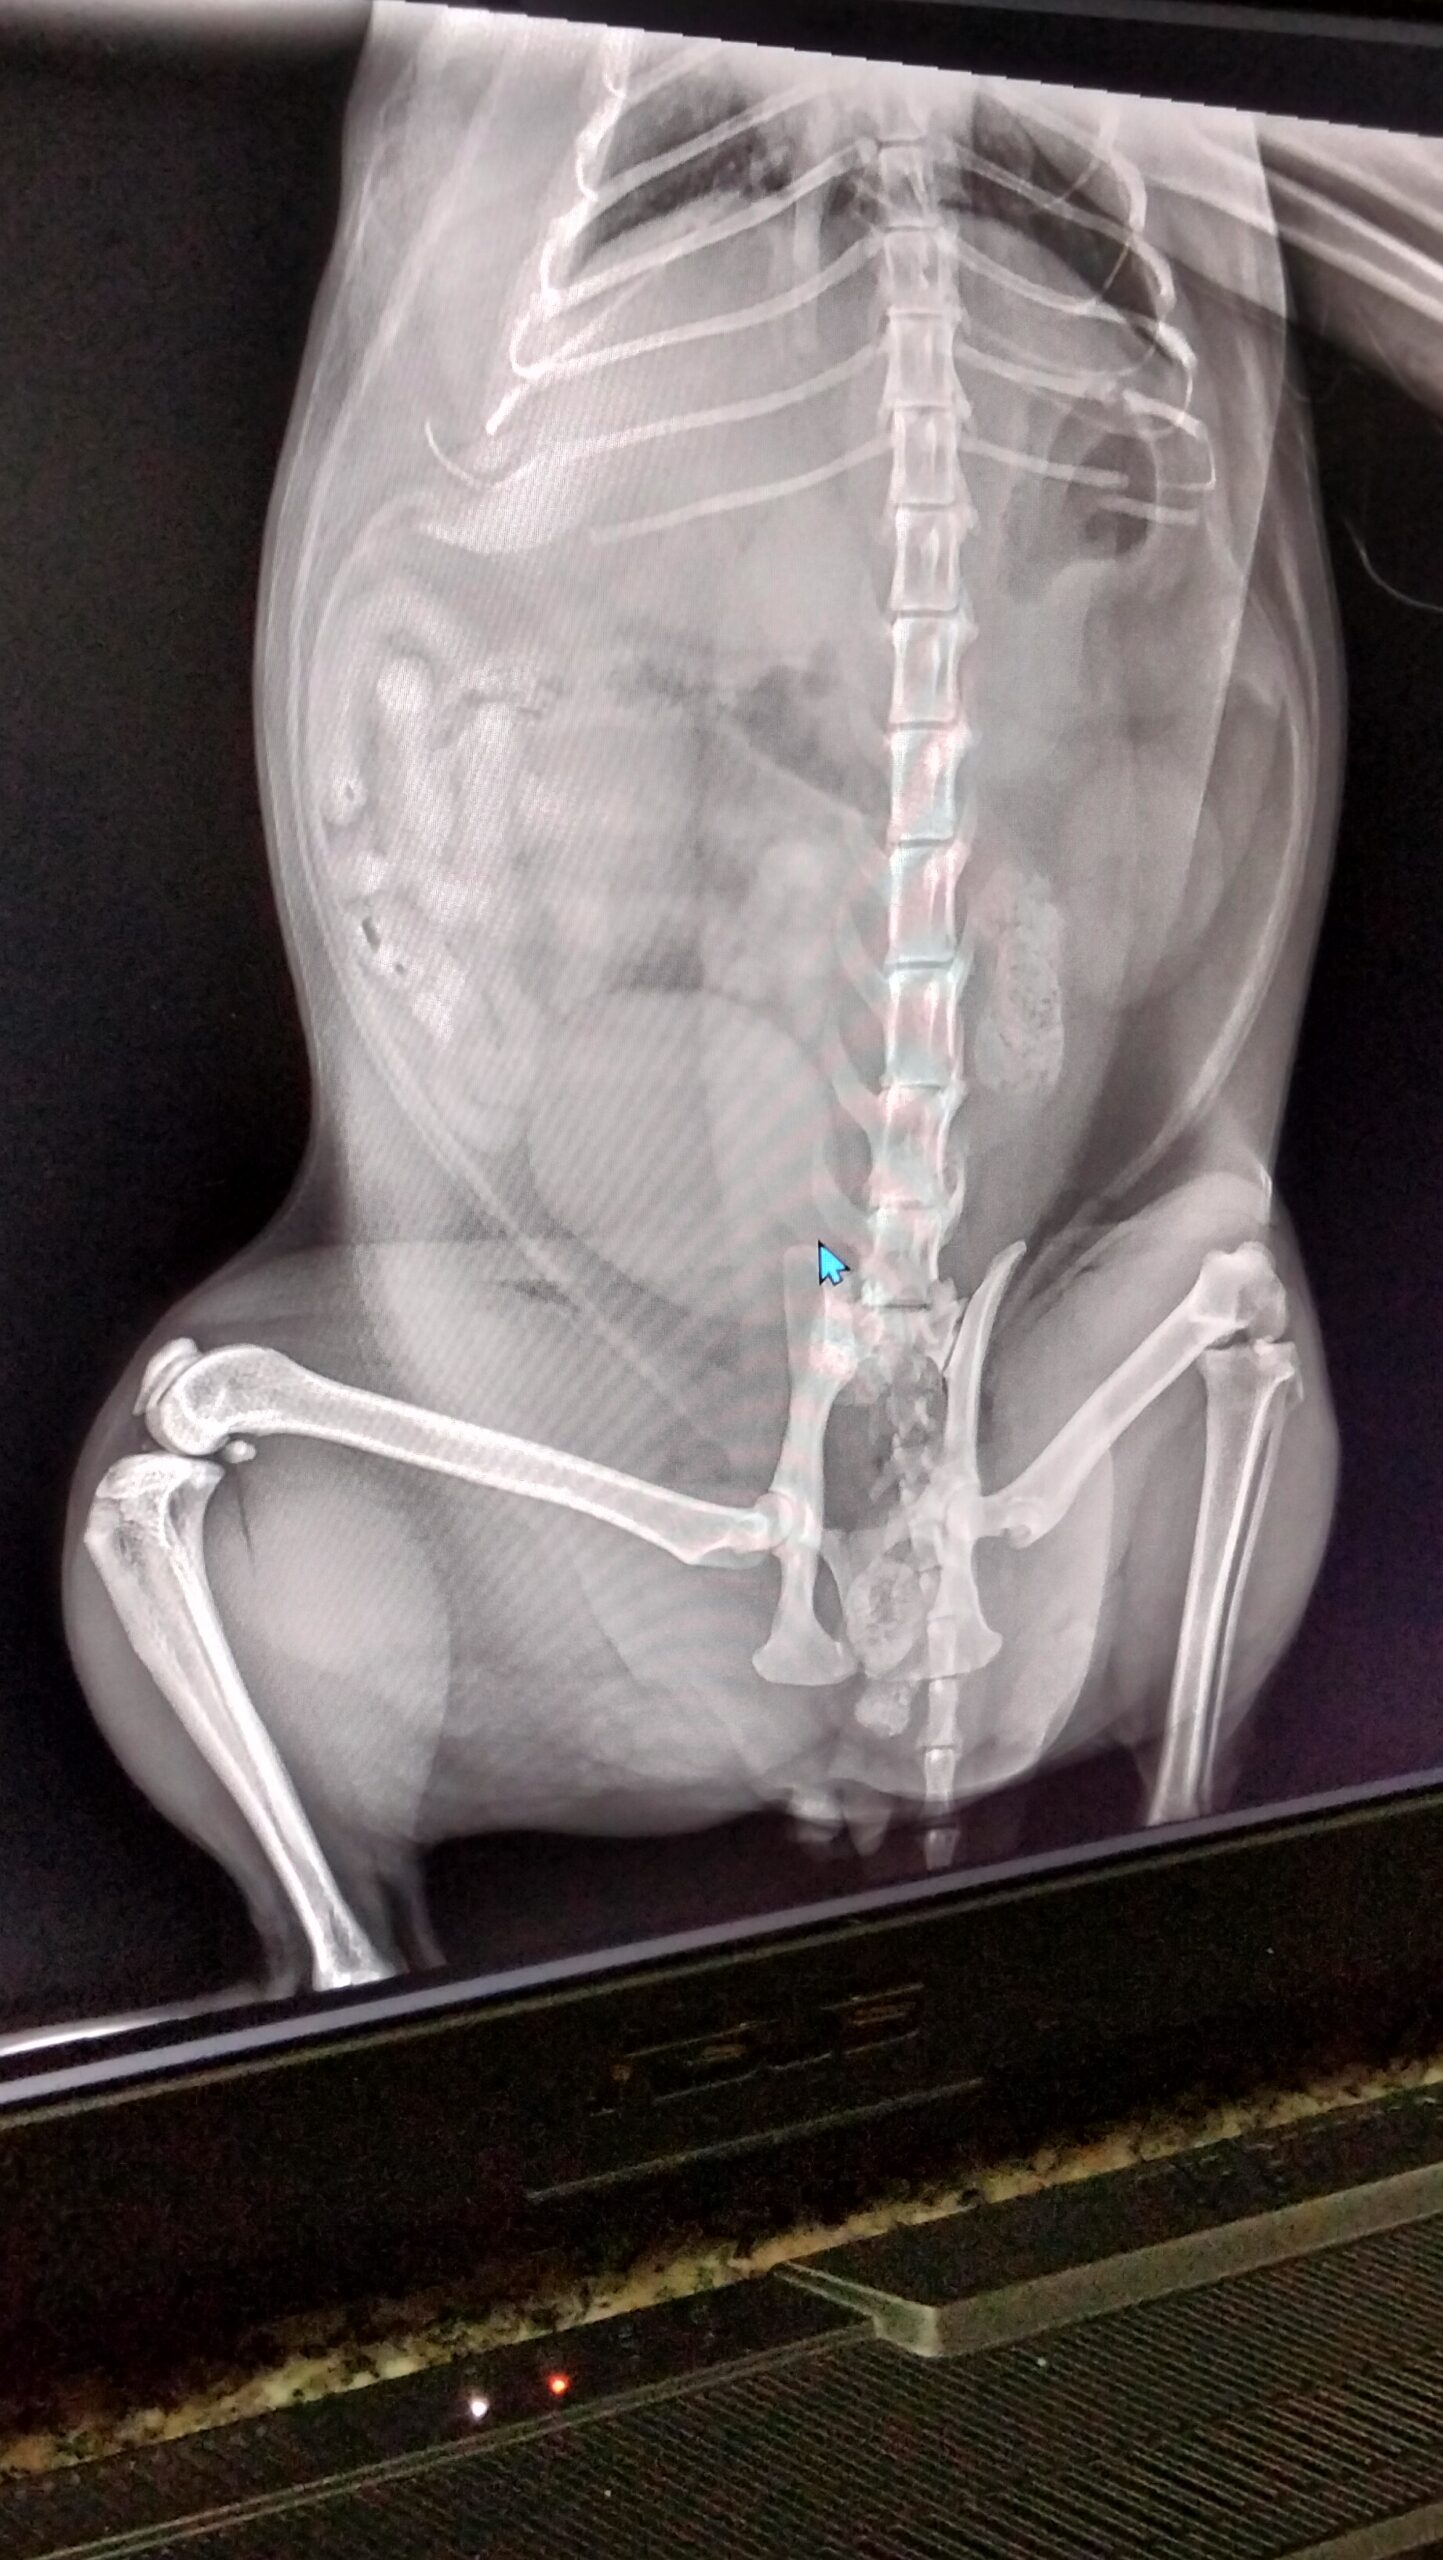

أشعة إكس راي

قطي كان بيتحرك بشكل حريص و بطئ عملت اشعه اكس راي و دكتور قالي كسر في الحوض و دكتور تاني قالي التهاب في الفقرات القطنية

اعمل ايه